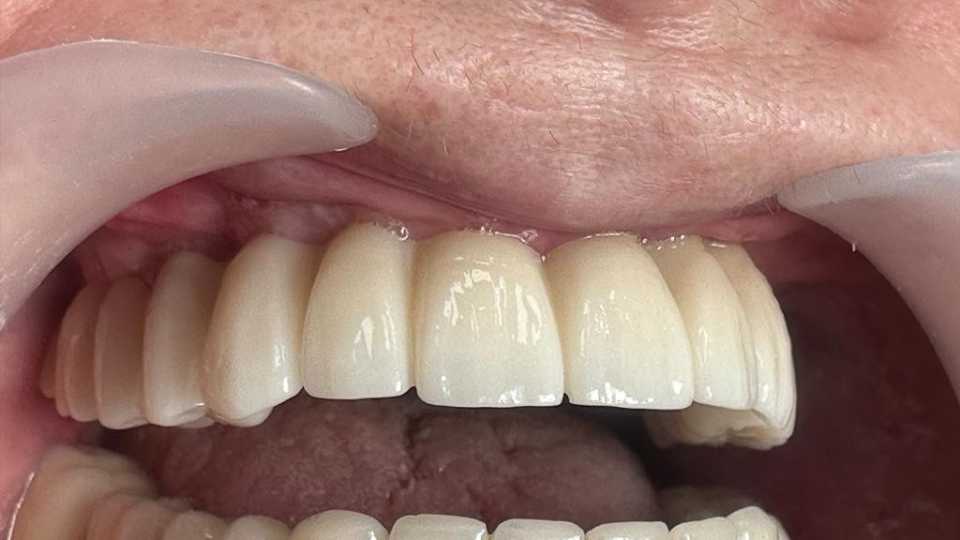

Pentru a răspunde nevoilor sale, s-a optat pentru utilizarea unor implanturi orale speciale: 4 implanturi zigomatice, 2 implanturi pterigoide și 1 implant standard. Această abordare a permis reabilitarea completă a arcadei dentare superioare printr-o lucrare protetică fixă, înșurubabilă, realizată din ceramică pe suport de zirconiu.